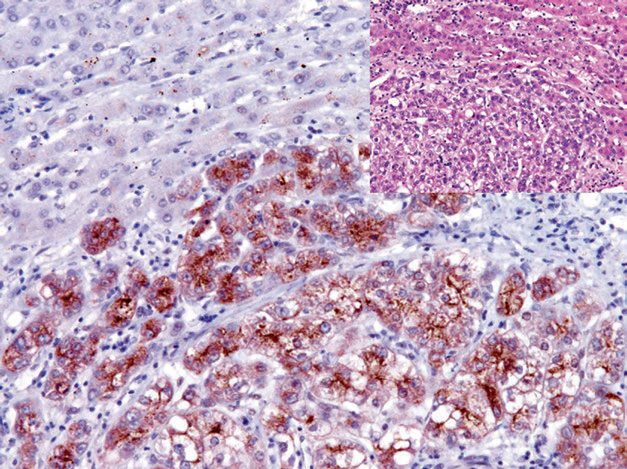

图1. 肝细胞癌,免疫组化CD34,窦内皮细胞阳性。

图3. 肝细胞癌,免疫组化Glypican-3阳性;背景中非肿瘤性肝组织为阴性。

迈迈:”Arginase-1是肝细胞腺瘤及肝细胞癌的敏感性和特异性标记物,可联合Glypican-3和Hepatocyte用于原发性肝细胞癌与转移性肿瘤及胆管癌的鉴别诊断。Glypican-3表达于胚胎性肝、肾、肺组织和胎盘组织滋养叶细胞层中,而其他正常组织不表达,在肿瘤性组织肝细胞癌、卵黄囊瘤、绒毛膜癌、黑色素瘤中可见阳性表达,联合使用CD34可用于鉴别良恶性肝细胞肿瘤。”